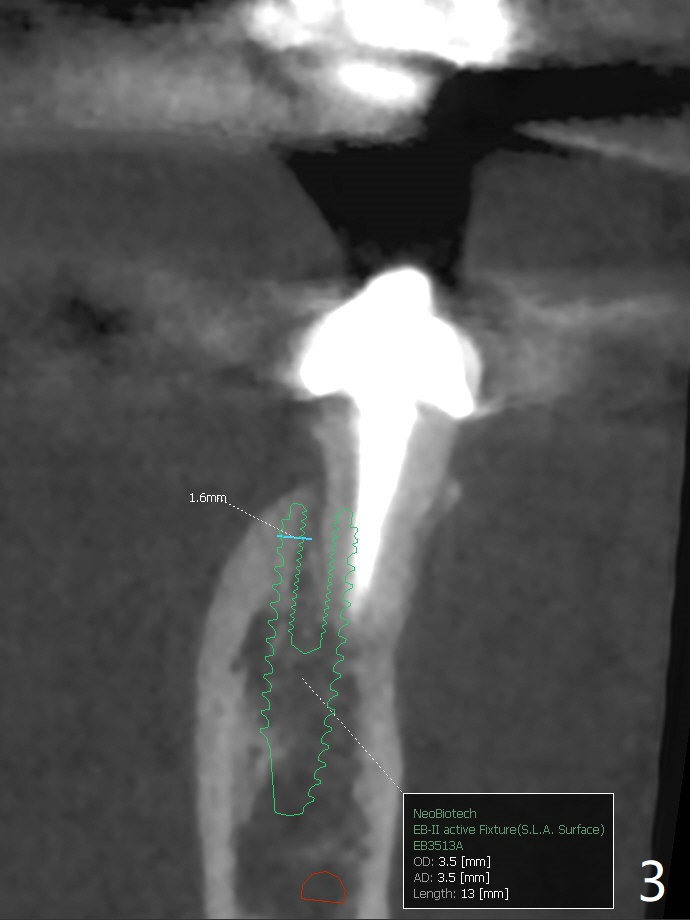

A 53-year-old woman develops an abscess lingual to the tooth #20 before #19 final restoration. Reanalysis of CT taken 5 months earlier shows the thin buccal plate (Fig.1 B). A 3.5x13 mm bone-level/3.5x17 mm tissue-level implant should be lingually placed (Fig.2,3). Socket shield will be performed (Fig.4 *); the lingual cortex removed with Lindamann bur (red) for ~1.6 mm. Initial osteotomy will be conducted in the lingual wall of the socket coronally (Fig.5 white arrow); after penetration, the initial drill will change the trajectory (Fig.6).